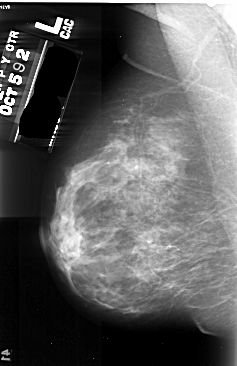

A_1029_1.LEFT_MLO

DATE_OF_STUDY 5 10 1992

PATIENT_AGE 39

DENSITY 4

LEFT_MLO LINES 5476 PIXELS_PER_LINE 3541 BITS_PER_PIXEL 16 RESOLUTION 42 NON_OVERLAY

FILE: A_1029_1.RIGHT_MLO.OVERLAY

TOTAL_ABNORMALITIES 1

ABNORMALITY 1

LESION_TYPE CALCIFICATION TYPE PLEOMORPHIC DISTRIBUTION CLUSTERED

ASSESSMENT 4

SUBTLETY 3

PATHOLOGY MALIGNANT